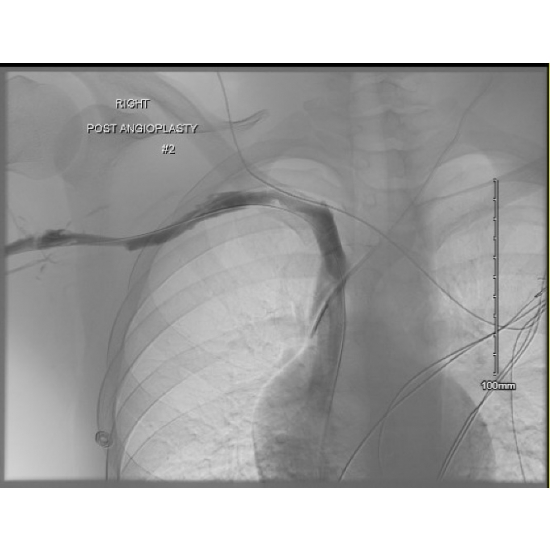

Post-Angio

Case Photo #4